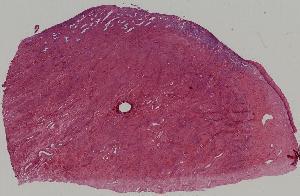

22. Chronic inflammation of cervix